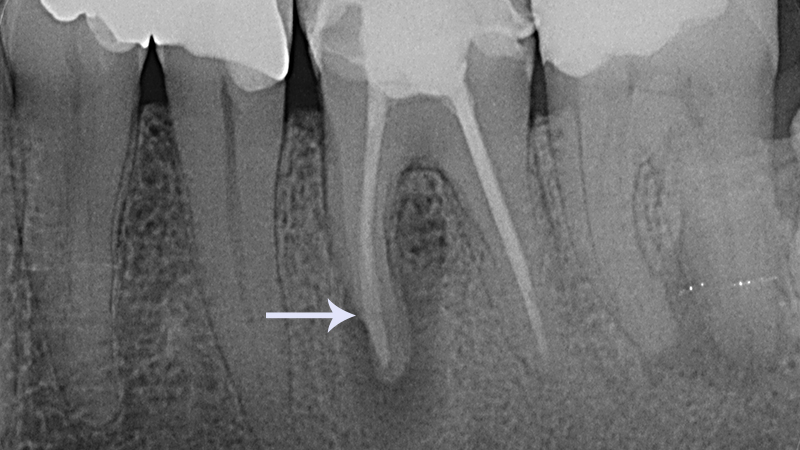

Fratura radicular

As fraturas radiculares podem ocorrer em diferentes níveis:

- Terço apical: Geralmente apresentam prognóstico favorável, com maior probabilidade de cicatrização espontânea.

- Terço médio e cervical: Demandam atenção especial, pois podem comprometer a estabilidade do dente.

Nos casos mais graves, a extração pode ser necessária. O diagnóstico é feito por meio de radiografias, sendo o tratamento orientado pela localização e extensão da fratura.